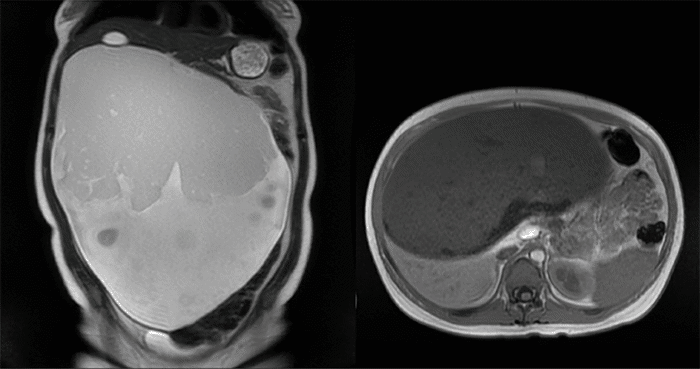

Figure 2. T2-Weighted MRI. Published with Permission

Large (32.5 x 28.1 x 14.1 cm) retroperitoneal mass with both cystic and solid components containing internal fat

A 33-year-old woman presented after referral to the surgical oncology service at eight weeks gestational age with an incidentally found large abdominal mass on initial obstetrical ultrasound (Figure 1). Magnetic resonance imaging (MRI) of the abdomen identified a 32.5 cm x 28.1 cm x 14.1 cm mass with cystic and solid components, and internal fat, demonstrating significant mass-effect on the liver, gallbladder, inferior vena cava (IVC), bilateral kidneys, and with displacement of intestines from the right hemiabdomen into the left (Figure 2). This was her first pregnancy, and the patient described approximately one year of vague nondescript symptoms including early satiety, constipation, and weight-gain—some of which she had attributed to her pregnancy. Her family history was significant for breast cancer in a paternal aunt. Computed tomography (CT) imaging was performed due to the possibility that this retroperitoneal mass was harboring malignancy as well as for preoperative planning. Imaging showed a large, well-circumscribed 16 x 20 x 30 cm cystic mass containing fluid levels, with a separate 2.4 x 1.0 cm well-circumscribed mass along the celiac axis, without evidence of metastasis or obvious invasion (Figure 3). No specific tumor markers were obtained. Due to concern for malignancy and worsening mass-effect on intraabdominal organs in the setting of viable intrauterine pregnancy, the decision was made to proceed with surgical resection prior to the second trimester.

Ultrasound is often the initial modality used in diagnosis, as it can be used to differentiate between solid and cystic components and may be able to detect calcification from teeth and/or bone, or posterior sound attenuation from sebaceous material and hair within a cyst cavity.4,5 It can be difficult to determine the true location of masses by ultrasound alone, specifically while differentiating between ovarian and retroperitoneal tumors.10 Further imaging with computed tomography (CT) or magnetic resonance imaging (MRI) is often needed for diagnosis and to determine potential malignancy.5,8,10 MRI was performed in our patient to initially characterize the mass,  and CT imaging was employed to further evaluate potential malignancy and preoperative planning. Characteristic findings on CT imaging include well-marginated, multilobulated complex masses with both cystic and solid components; and fluid, fat, soft tissue, and bone densities observed in the retroperitoneal space. The presence of hypoattenuating fat within the cyst or calcifications in the cyst wall is highly suggestive of cystic teratoma.5,10 Our patient's CT imaging demonstrated a large 16 x 20 x 30 cm well-circumscribed cystic mass with fluid levels, without internal calcifications or fat density identified, that did not appear to arise from adjacent organs or demonstrate invasion and was concerning for mesenteric lymphangioma per radiology review (Figure 3). The second 2.4 cm x 1.0 cm mass was well-circumscribed and appeared to contain proteinaceous or hemorrhagic material. Absence of mature tissues, sebum, and occurrence in childhood years have been reported to be predictors of malignant change.5 MRI has been used, specifically during pregnancy, to avoid radiation exposure, as these lesions have a high fat content and appear hyperintense on T1-weighted images.5,8 The MRI performed on our patient demonstrated a 32.5 x 28.1 x 14.1 cm arising from or abutting the inferior surface of the liver, with both cystic and solid components with evidence of internal fat, with differential diagnosis considering fibrolamellar hepatocellular carcinoma, hepatic adenoma, giant hemangioma, leiomyosarcoma of the mesentery, or a cystic teratoma per radiology report (Figure 2).